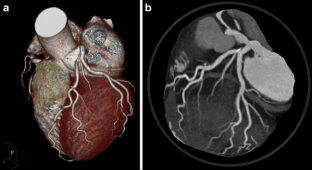

Fig. 2